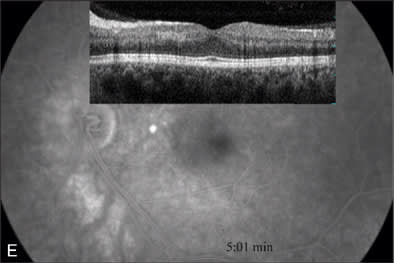

At our initial examination in August 2008, corrected visual acuity was 20/30 in the right eye and 20/50 in the left, with normal ocular pressure in both eyes. There were no rubeosis irides in either eye. Fundus examination appeared normal in the right eye while the left eye revealed a typical nonischemic CRVO (Figure 1A). Fluorescein angiography of the left eye (Figure 1B to 1E) showed generalized dilated, tortuous retinal veins, intraretinal hemorrhages, peripheral retinal non-perfusion areas, and microvascular leakage at the macula (Figure 1E, arrow). Despite the peripheral retinal ischemia, the macula itself was not ischemic at the first visit, as evidenced by the early phase FA showing 2 cilioretinal arteries supplying the fovea (Figure 1C, arrow). Spectral domain OCT (OPKO-OTI, Miami, FL.) confirmed the diagnosis of cystoid macular edema (CME). The patient got intravitreal bevacizumab (Avastin) injection (1.25 mg/0.05 mL) at the first visit.

At the 5-month follow-up visit in February 2009, corrected visual acuity remained 20/20 in the left eye, with normal ocular pressure in both eyes. There were no rubeosis irides in either eye. Fundus examination appeared normal in the right eye with improvement in the appearance of the retinal vasculature in the left (Figure 2A). Fluorescein angiography of the left eye (Figure 2B to 2E) showed resolution of the CRVO characteristics (dilated, tortuous retinal veins, intraretinal hemorrhages, peripheral retinal non-perfusion areas) with no microvascular leakage at the macula. Spectral OCT confirmed no cystoid macular edema (Figure 2E).